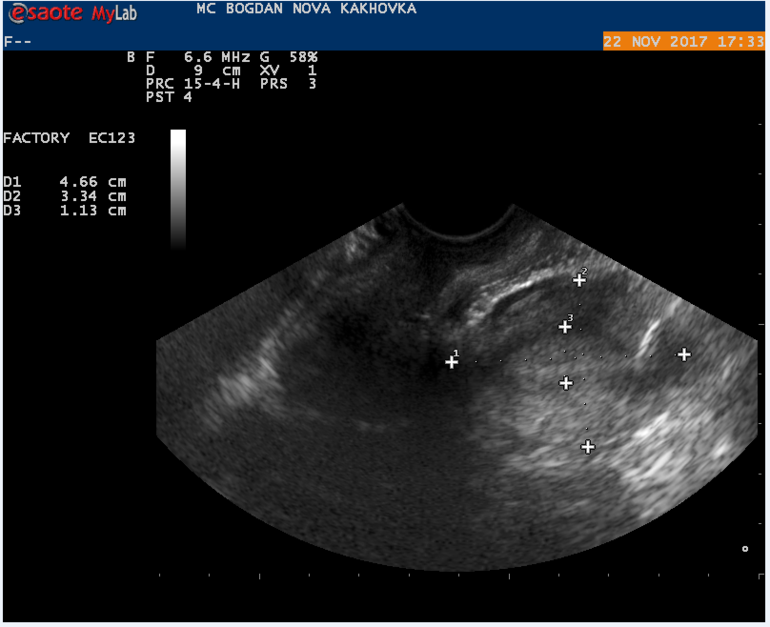

Мой результат УЗИ на 16 ДЦ Кто что может сказать? Тест на О положительный на 13 и 14 ДЦ.

Могли желтое тело не увидеть, а мог и сдуться фоликул, и не было овуляции. А то что эндометрий хороший - еще не показатель, у меня при здутии фолликула и при лютеинизации фолликула он тоже был отличный и соответствовал второй фазе.

Может не увидели жт? Или не успело сформироваться.. Лично не сталкивалась, но читала, что бывает его не видят. Ведь эндик второй фазы у вас.

Какой день имел в виду Г? 1 дпо? По идее узи должно хорошо отображать картину в любой день.. Но просто видимо бывает, что узист что-то не разглядит, может аппарат не очень. У вас О вероятно была на 15 дц. А до этого не делали узи в этом цикле? Для точности О можно и прогик сдать. Но нам важнее конечно хгч))

в протоколе узи не слова о наличии доминантного фолликула, поэтому вряд ли была или будет овуляция в ближайшие дни

судя по узи овуляции не было,доминантного фолликула нет. хотя желтое тело может позже сформироваться